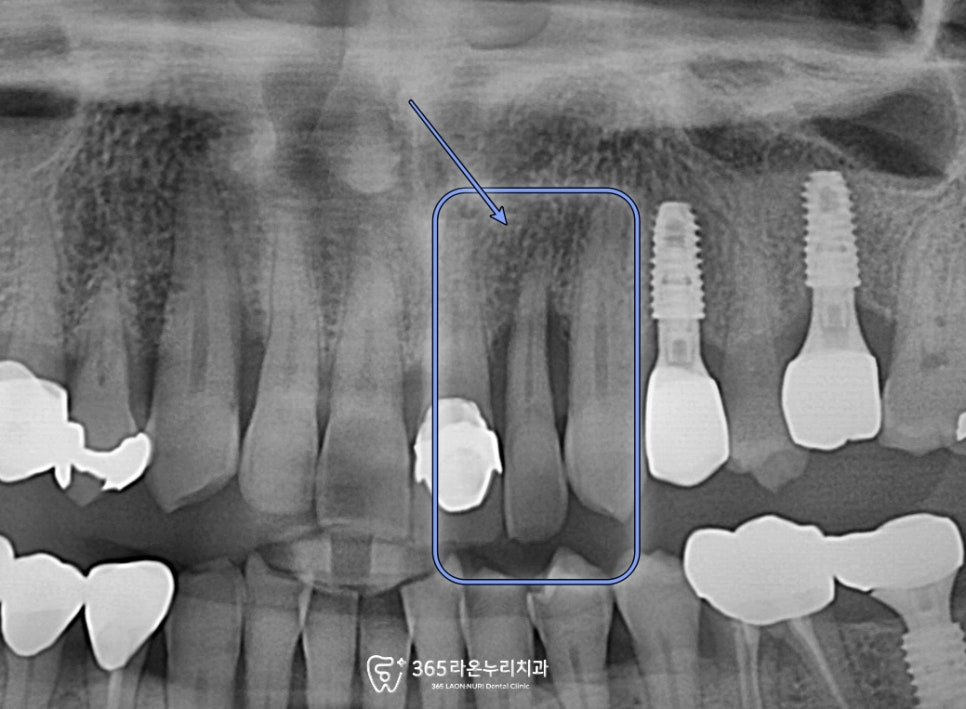

사진을 보면 표시한 치아에

잇몸인 내려간거 빼고는

겉모습으로 봤을 때는

큰 문제가 없어 보이는데요.

하지만, 지속적인 불편감이 있다면,

치근단 염증을 의심해 볼 수 있습니다.

그래서 오산 치과 에서

앞니 주변의 치조골을

보면서 설명드리겠습니다.

엑스레이 사진을 보면

세균 감염이 일어나면서,

염증이 발생할 수 있습니다.

그래서 치조골이 소실되어

뿌리를 잡아주지 못해

흔들리고 있는 모습까지

확인할 수 있었습니다.

현재 심각한

잇몸 염증이 있었기에,

발거 후 앞니 임플란트 과정을

오산 치과 에서 설명드리겠습니다.